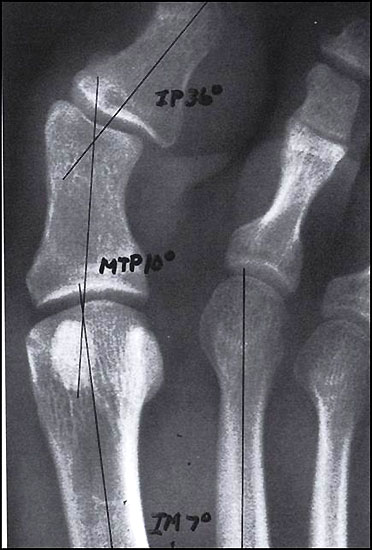

Wenn durch das Anspannen der Muskulatur der 1. Strahl zu einem starren Hebel wird und aussteift, empfehlen wir auf die Durchführung einer TMT-I-Arthrodese zu verzichten und z.B. eine proximale Korrekturosteotomie durchzuführen. So ist nach unserer Auffassung bei jeglicher Dorsalbewegung des 1. Strahles (Instabilität) trotz Anspannung der Peronealmuskulatur (wie beschrieben) die Indikation zur Lapidusarthrodese unabhängig vom Intermetatarsalwinkel gegeben. Bei der Beurteilung des a.p.-Röntgenbildes unter Belastungsbedingungen dient die Bestimmung des Hallux valgus interphalangeus-Winkes und des distalen Artikulationswinkels ggf. zur Indizierung einer additiven Akin-Osteotomie (Abb. 4). Die Stellung des proximalen Artikulationswinkels legt im Falle einer bereits praeoperativ bestehenden Vergrößerung nach Korrektur des Intermetatarsalwinkels eine Korrektur durch eine Reverdin-Green-Laird-Osteotomie nahe (Abb. 5). Die Größe des Intermetatarsalwinkels I/II beeinflusst je nach Größe bei stabilem 1. Strahl die Wahl des jeweiligen Operationsverfahrens.

Im Falle einer Insuffizienz des 1. Strahles wird in jedem Falle eine TMT-I-Arthrodese indiziert sein, hier dient der Intermetatarsalwinkel planerischen Aspekten im Sinne des Ausmaßes der Korrektur am Os cuneiforme I. Die Bestimmung des Metatarsus adductus-Winkels dient der Detektion eines Pes adductus. Im Falle des Vorliegens einer solchen Deformität sind ggf. auch Korrekturosteotomien an den kleineren Metatarsalia zu erwägen, um ausreichend Platz für die Einstellung des Metatarsale I in die Rectusposition zu erhalten. Ein weiteres wichtiges Kriterium in der a.p.-Projektion stellt das Längenverhältnis von Metatarsale I zu Metatarsale II dar, da bei der Durchführung der TMT-I-Arthrodese das Vorliegen einer Minusvariante häufiger die Gefahr einer postoperativen Transfermetatarsalgie birgt und hier unter Umständen über Modifikationen des operativen Vorgehens nachgedacht werden sollte. Hier besteht die Möglichkeit von alternativen Präparationsverfahren im TMT I oder aber der Durchführung einer Interpositionsarthrodese des TMT I zur Verlängerung des 1. Strahles. Alternativ können auch Verkürzungsosteotomien des 2. und 3. Strahles erwogen werden. Als indirekte radiologische Zeichen einer Insuffizienz des 1. Strahles kann ein Klaffen des Spaltes zwischen dem Os cuneiforme mediale und dem Os cuneiforme intermedium sowie eine Hypertrophie der Corticalaes des Metatarsale II gedeutet werden (Abb. 6).